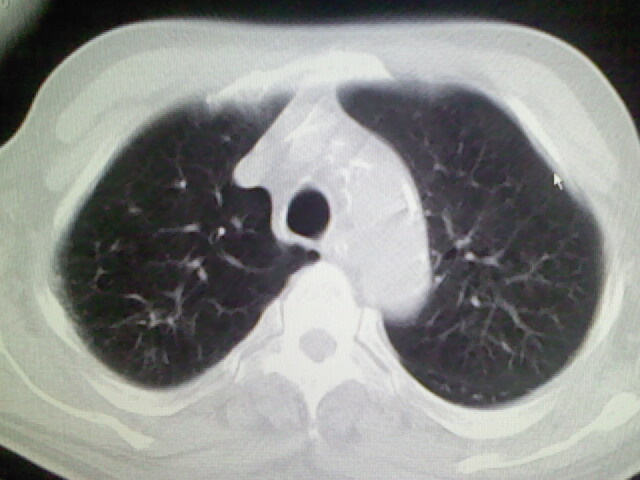

男,70岁,脑出血,长期卧床,左侧背部可触及肿块

考虑右肺及左肺下叶炎症。

考虑右肺及左肺下叶慢性炎症。

右侧肺部见片状密度增高影,边缘模糊。考虑炎症。另食管壁增厚。

右肺肺气肿并炎症。

右肺上叶前段病呈楔形,其尖端指向肺门,考虑肺动脉栓塞可能性大.